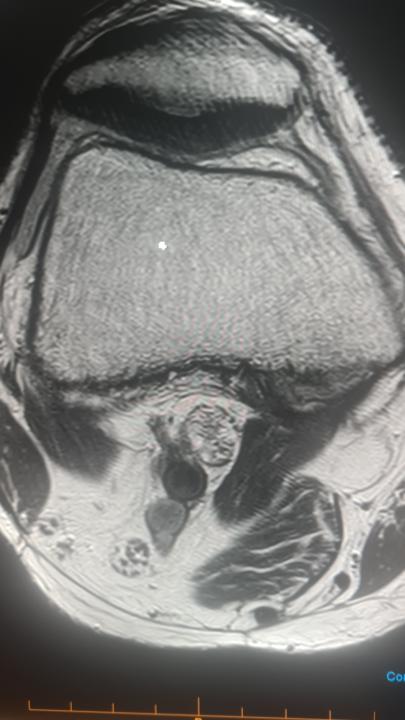

Could this be "black line sign" of cartilage?

Areas of cartilage PDW/PDW FS hypointense signal - possible areas of fissuring/cartilage degeneration? https://www.cmrad.com/cases/1089538934

0 likes • Mar 7

@Christoph Agten